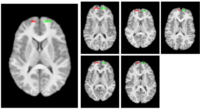

Build a structural atlas from all sub jects’ T1 images. Seed regions for tract endpoints are manually delineated in the structural atlas and then mapped from the atlas to each individual. Automatically segment white matter tracts and quantify diffusion properties using volumetric pathway analysis.

The structural atlas built from the five T1 images with manually outlined frontal forceps seeds (left). The seeds mapped to each of the individual cases (right).